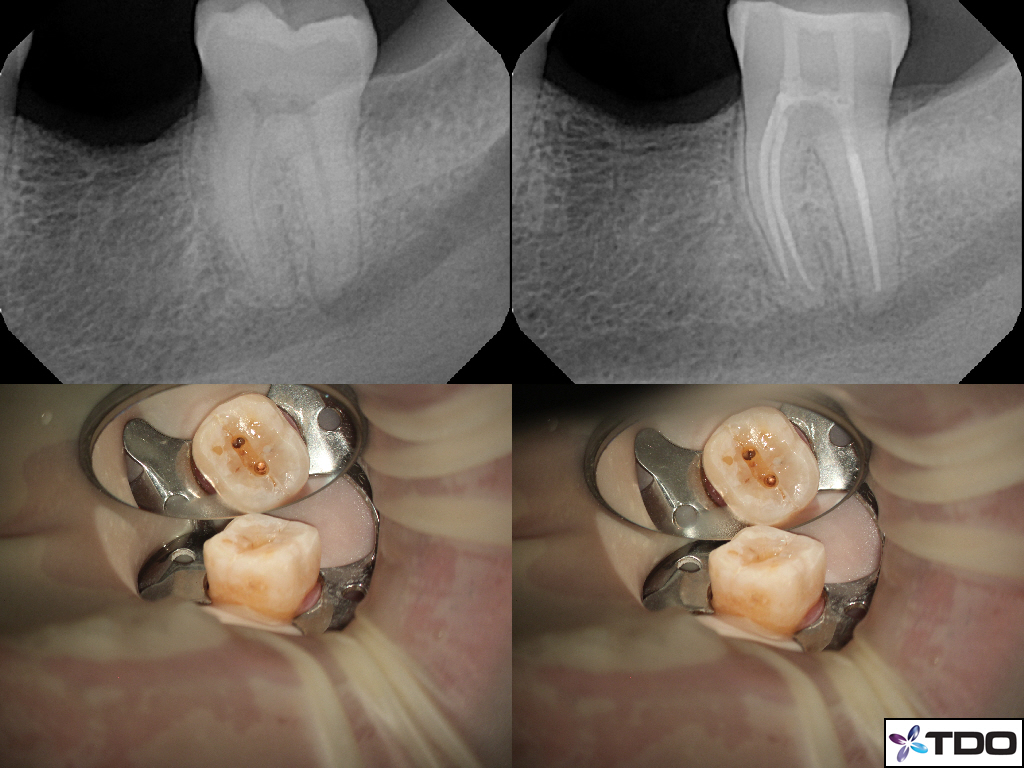

These cases show a level of commitment to conservative endodontics rarely seen in endo today. Plus the restorative excellence is inspiring and should stimulate all endodontists to up their game and help others realize how important the restorative aspect of endodontics is.